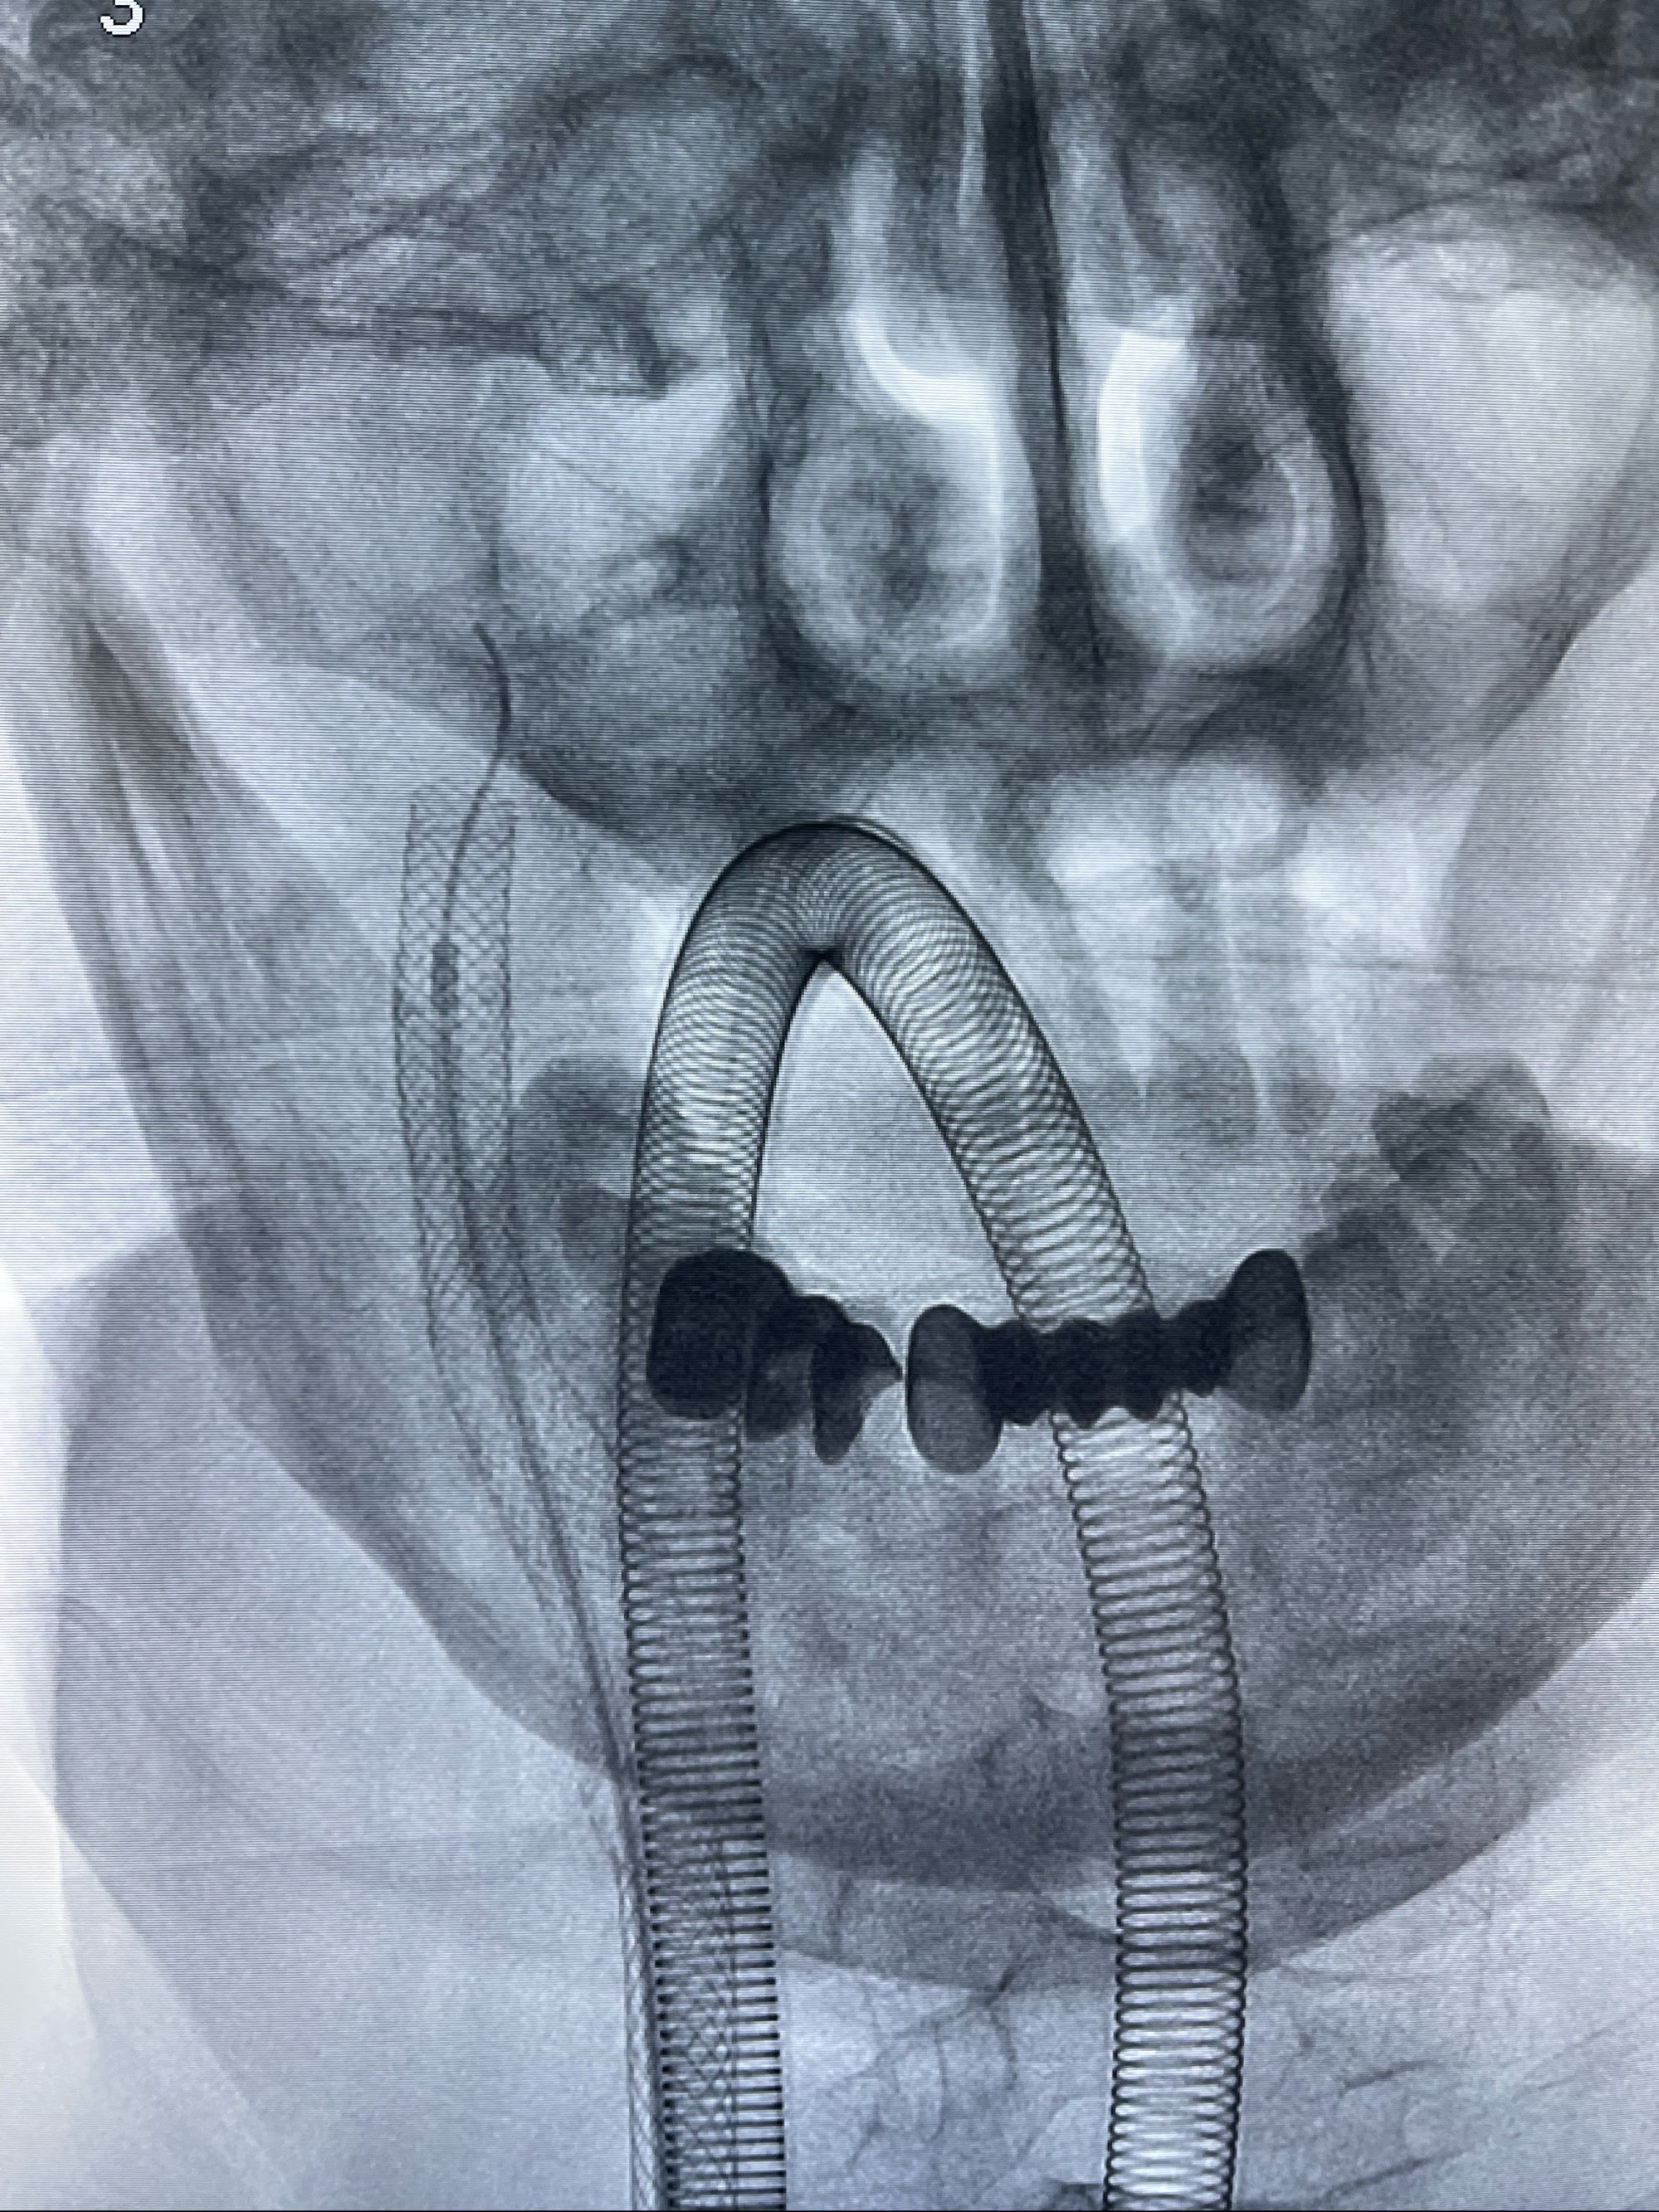

重新行“路径图”,支架导管在微导丝引导下超选择性插入至右侧颈内动脉眼段,4.5-50mmLeo支架释放,远心端位于海绵窦段,近心端位于岩骨段狭窄段以近

即刻造影显示支架贴壁佳

路径图下,5.5-50mmLeo支架导管在微导丝引导下超选择性插入远段Leo支架内

两枚支架部分重叠

多次确认支架位置及打开贴壁情况

支架完全打开,近心端位于原颈动脉支架远心端内

麻醉苏醒佳,遵嘱活动!

术后给予替罗非班300ug/h维持,序贯阿司匹林100mg➕泰嘉75mg口服